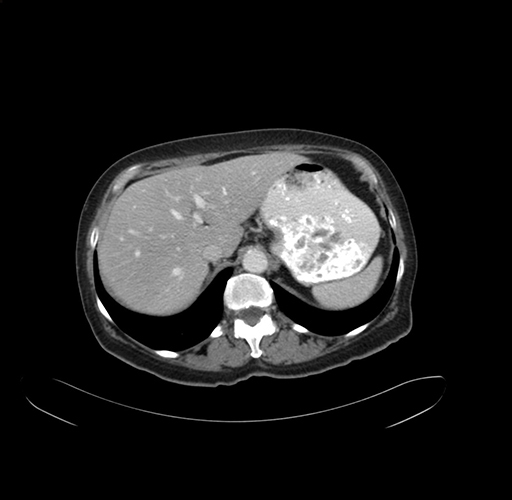

Axial Venous